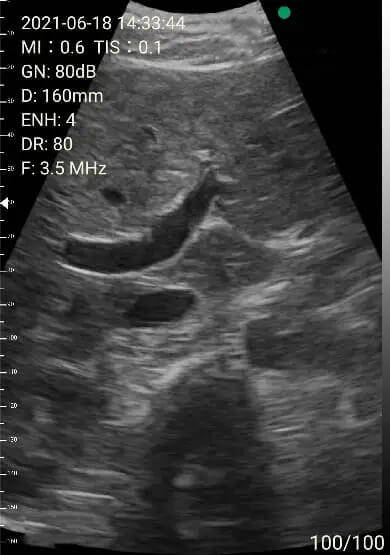

2. Abdomen review

Left lobe of liver

Portal area

Right lobe of liver

Images of thyoid scan on a 35-year-old healthy man.